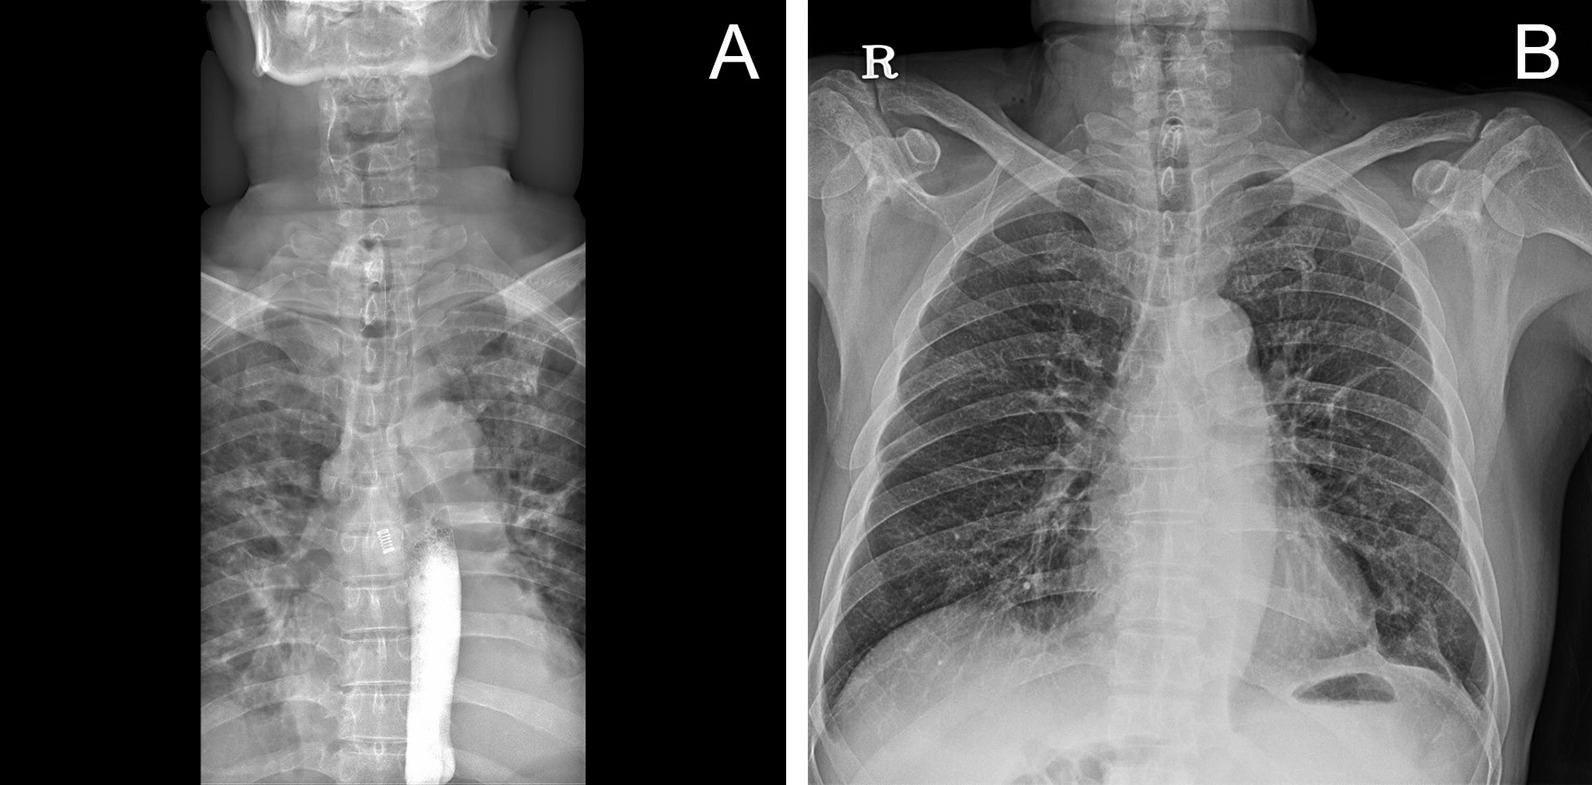

We describe the case of a 66-year-old man with tracheal rupture with thyroid cartilage fracture due to cultivator handle who was treated with veno-venous ECMO. This case reflects the role and limitations of veno-venous ECMO, in which patient survival was possible with a bi-femoral configuration while also ensuring a clear airway.

我们描述了一名 66 岁男性患者的病例,该患者因手扶耕耘机把手导致气管破裂和甲状软骨骨折,接受了静脉-静脉 ECMO 治疗。该病例反映了静脉-静脉 ECMO 的作用和局限性,其中双股静脉 ECMO 配置可确保患者存活并保持气道通畅。